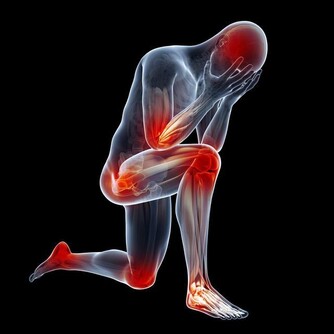

骨質疏鬆即骨質疏鬆症,是多種原因引起的一組骨病,骨組織有正常的鈣化,鈣鹽與基質呈正常比例,以單位體積內骨組織量減少為特點的代謝性骨病變。在日常的生活中,我們最常見的骨質疏鬆的症狀就是骨頭疼痛,身長縮短、駝背,容易骨折,還有就是呼吸功能下降。

1、體育鍛煉:通過運動,骨的生長可能得到特別的調節。可以預防因不活動引起的丟失以及改善肌肉和增加靈活性,從而減少跌倒及其不良後果。